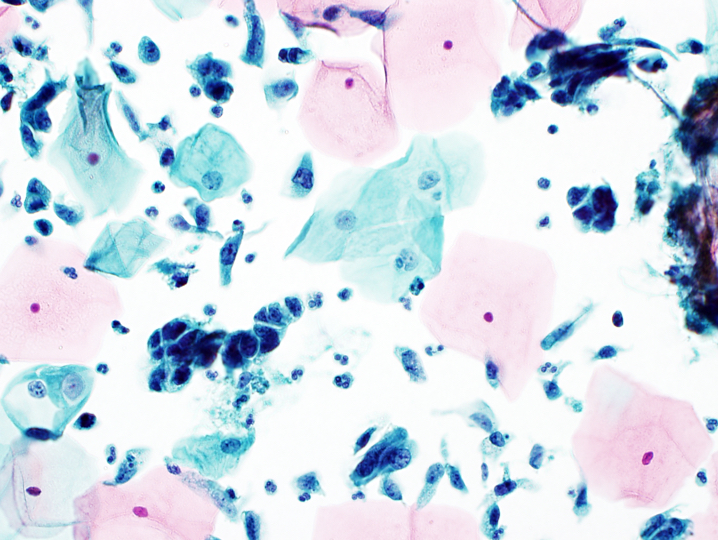

- Atypical endometrial cells

- Atypical endometrial cells are generally not further classified as favor neoplastic because this distinction has been shown to be poorly reproducible

- Cells occur in small groups, usually 5 - 10 cells per group

- Nuclei are slightly enlarged compared with normal endometrial cells

- Mild hyperchromasia and chromatin heterogeneity

Cytology images